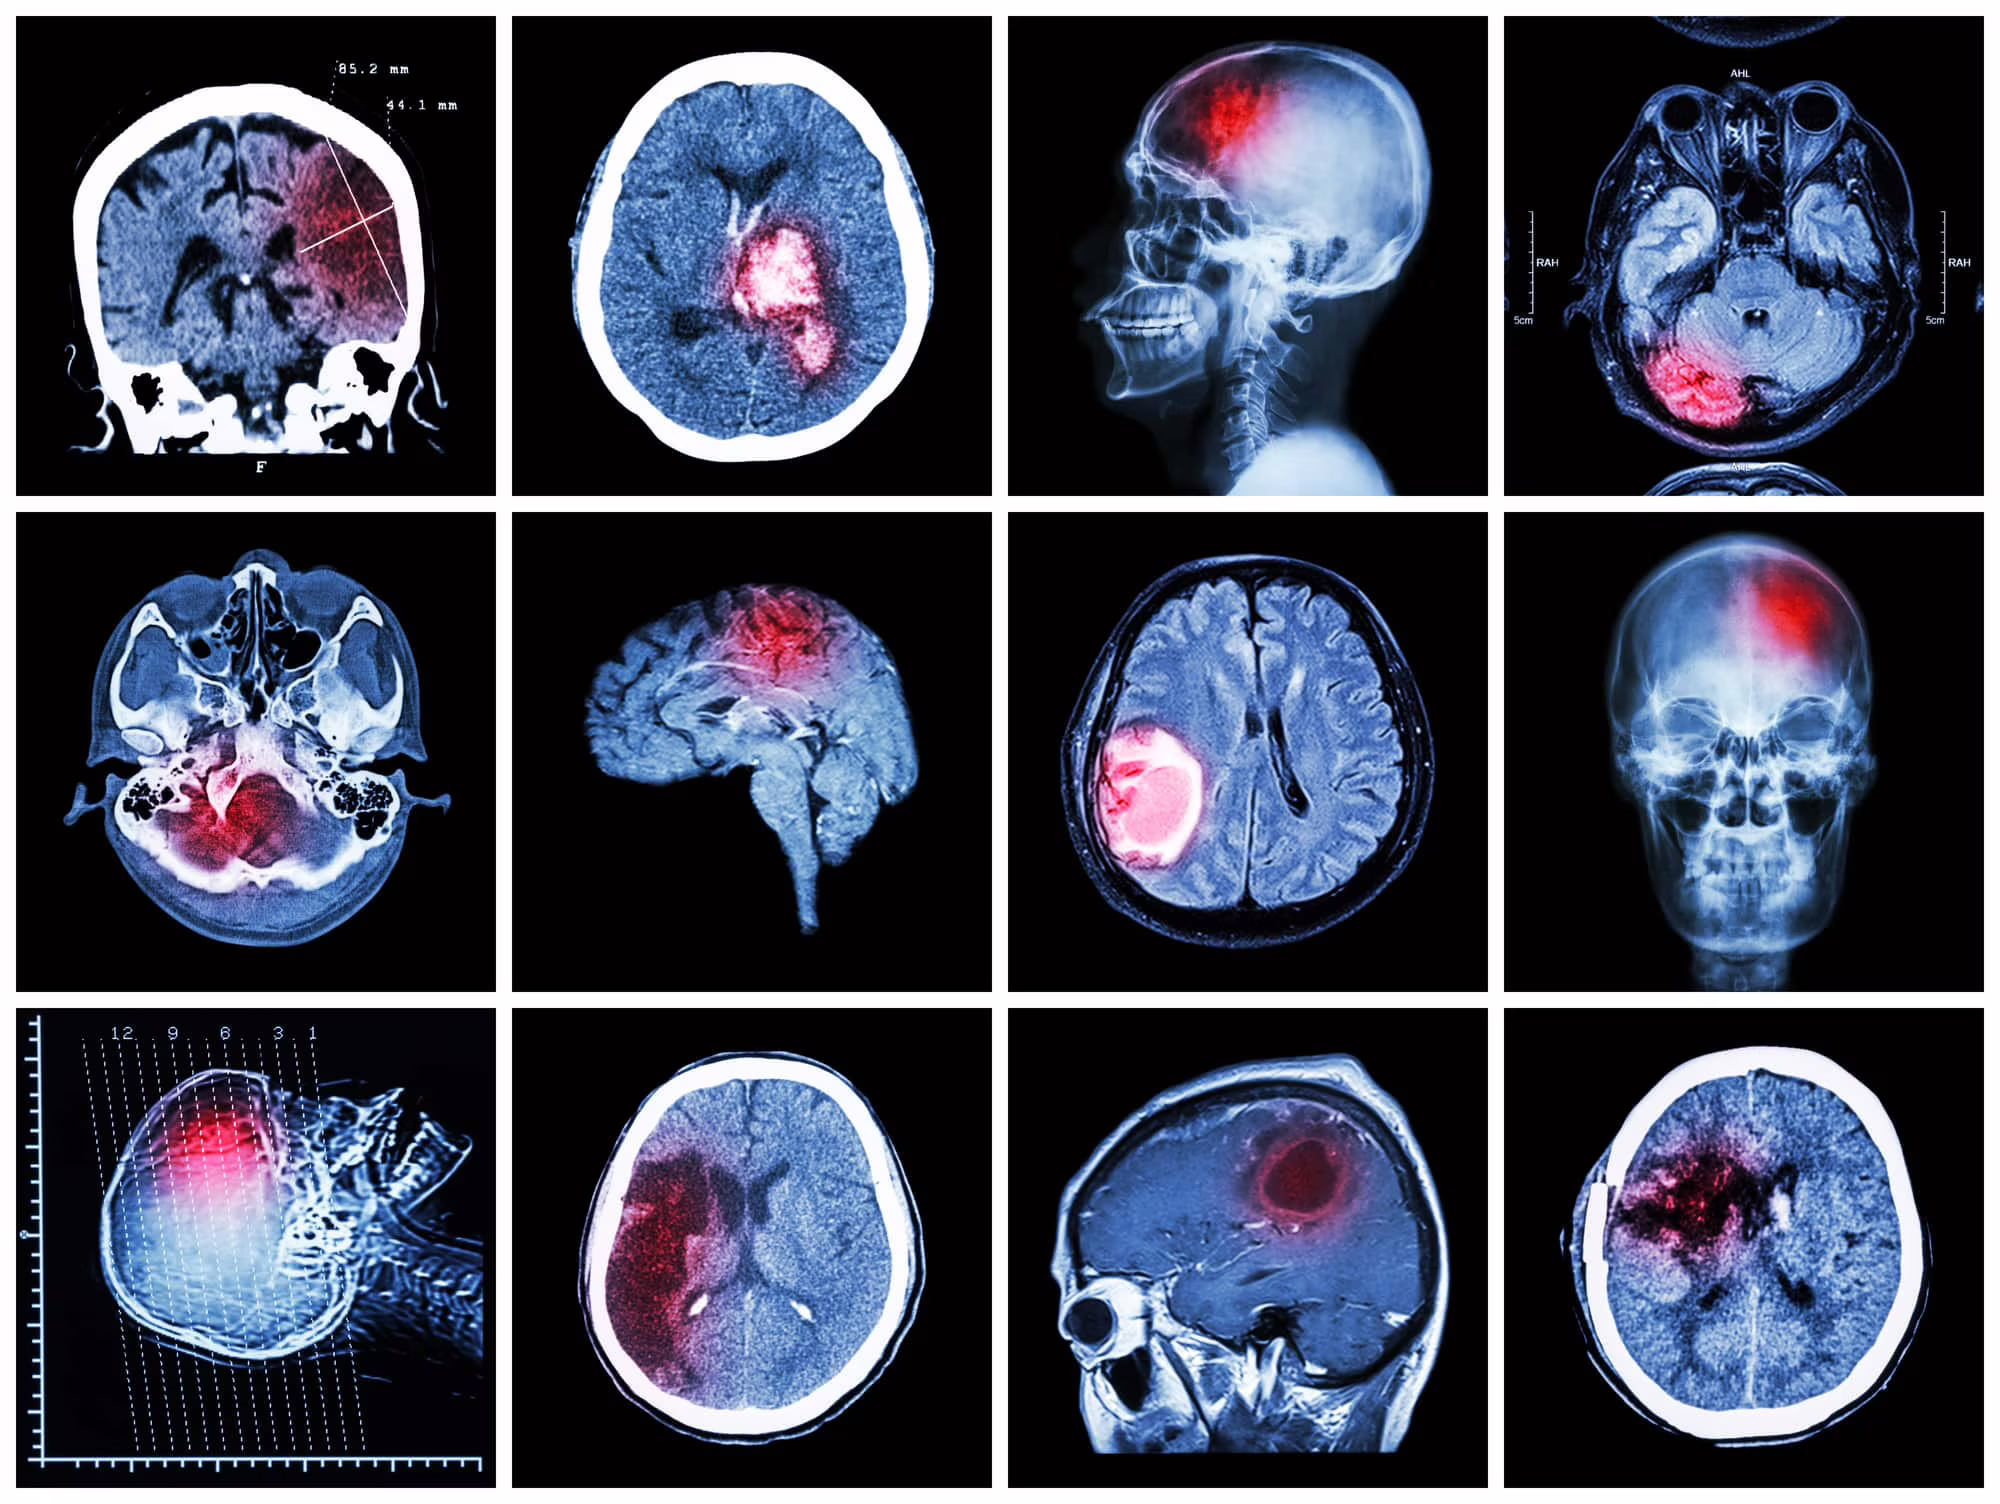

Glioblastoma: dieta innesca autodistruzione del tumore

Recentemente un team di ricercatori ha scoperto che rimuovendo dall’alimentazione alcuni aminoacidi, in un gruppo di topi affetti da glioblastoma, le cellule cancerose hanno iniziato a morire attraverso un processo chiamato ferroptosi. Inoltre, i topi con la nuova dieta alimentare risultano più ricettivi ai farmaci che innescano la stessa tipologia di morte nelle cellule tumorali. Questo porta a buoni risultanti che potrebbero essere applicati per combattere la malattia negli esseri umani.

Cos’è il glioblastoma?

Il glioblastoma è la tipologia più comune di cancro al cervello negli adulti. La malattia ha un elevato tasso di letalità e non presenta delle terapie definitive, ciò rende questo tumore uno dei più aggressivi. Per tale ragione, gli scienziati sono sempre alla ricerca di nuove terapie e di comprendere al meglio la biologia dei tumori. La morte cellulare è un processo normale all’interno del corpo umano e prende il nome di apoptosi: le cellule anormali o semplicemente non più necessarie vengono eliminate e riassorbite. Tuttavia, questo processo può non avvenire correttamente nelle cellule tumorali, il che permette loro di moltiplicarsi e causare gravi minacce per la salute.

In un nuovo studio, un team di ricercatori ha scoperto che le cellule coinvolte nella formazione del glioblastoma sono particolarmente sensibili alla ferroptosi. Ciò risulta fondamentale perché questa tipologia di cancro al cervello ha un tasso di mortalità quasi del 100% senza terapie attuali definitive. Risulta dunque visibile una possibile terapia futura che vede come protagonista la ferroptosi.